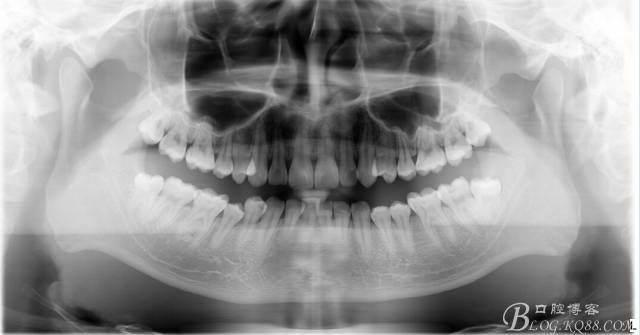

口腔檢查:37頰頜面齲洞,叩(+),探(+),冷熱測(cè)試與對(duì)照牙對(duì)比為敏感。17 27 47 均有不同程度齲壞,無明顯陽性體征。18 28 38 48 呈不同程度傾斜,38 48牙冠部分萌出。全口牙齒排列不整齊,口腔衛(wèi)生較差,牙石(++),部分牙齦發(fā)紅。X線檢查示37牙冠低密度影像累及牙髓,牙周間隙略增寬。

診斷:①37慢性牙髓炎 ②17 27 47頜面齲 ③18 28 38 48阻生牙 ④牙列不齊 ⑤牙齦炎